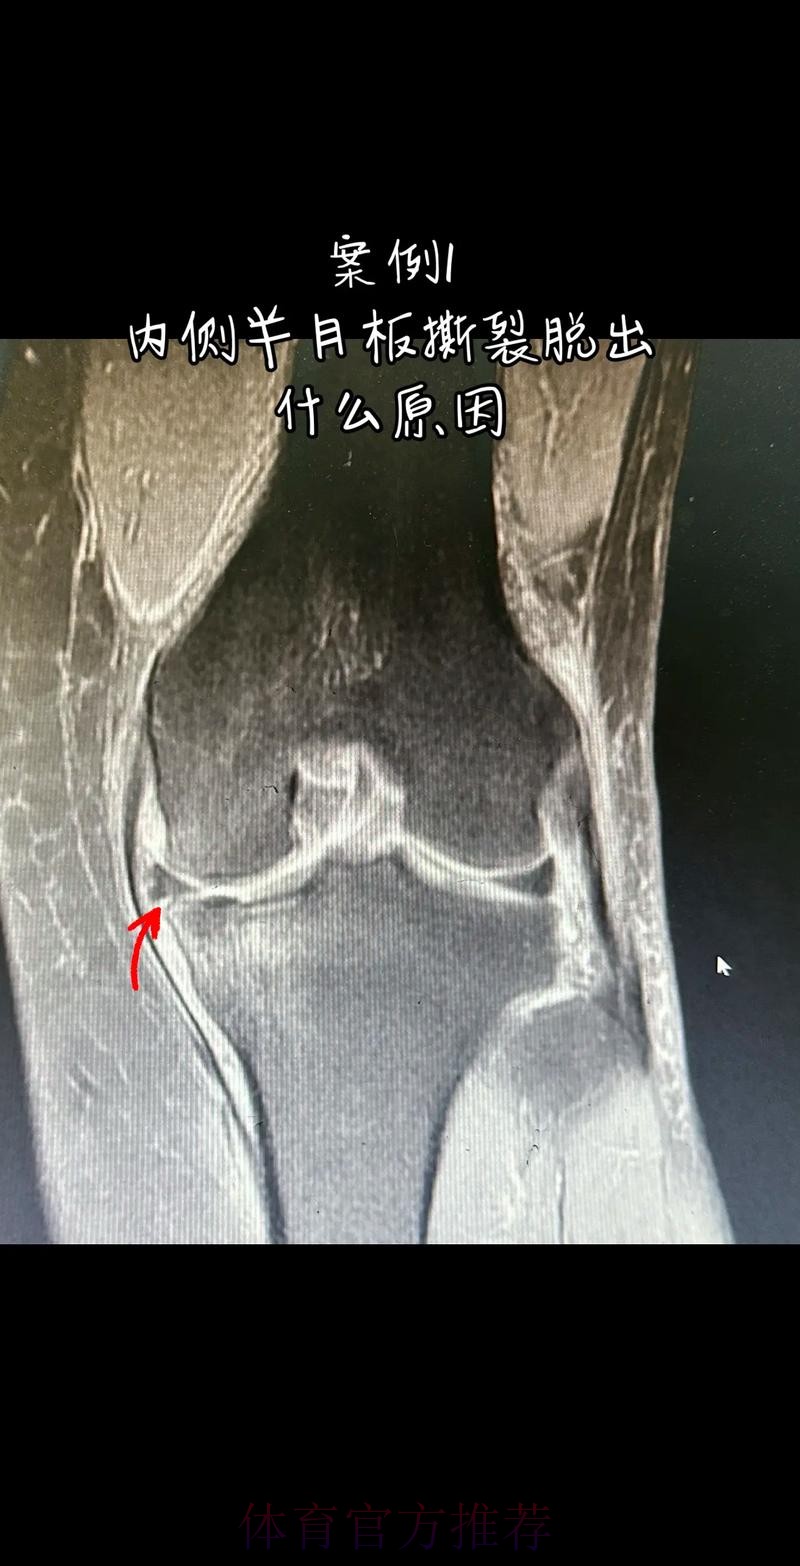

这条“官方 阿拉巴左膝内侧半月板撕裂 预计伤缺6-8周”的声明一出 不只是伤病通告那么简单 它背后牵动的是皇马后防体系的重塑 奥地利国家队备战计划的调整 以及一名顶级后卫职业生涯中一次关键的健康考验 对于已经习惯在高强度赛程中同时承担俱乐部与国家队重任的阿拉巴来说 这次伤病既是一次身体的警报 也是一次心理与战术层面的巨大挑战

在现代足球中 像阿拉巴这样能胜任中卫 左后卫 甚至后腰的多面手几乎是教练心中最理想的拼图 他不仅是后场的防守屏障 更是从后场发起进攻的节拍器 因此 当“左膝内侧半月板撕裂 伤缺6-8周”这样的诊断从官方口中给出时 对球队来说 就等同于在关键路段突然失去一块核心路基 球迷最直观的担忧是 皇马在这段时间是否还能保持防线稳定 奥地利是否在国际比赛日期间陷入被动 而对阿拉巴本人而言 这则官方消息意味着一个不得不按下暂停键的阶段 他需要重新面对恢复训练 康复计划 以及未来的竞技状态

阿拉巴在皇马的定位从来不只是“中后卫”这么简单 他可以在三中卫体系中担任左中卫 也可以在四后卫体系中出现在左后卫甚至拖后组织者的位置 在很多场次中 他会频繁前插 参与推进和组织 这意味着他在身体对抗 启动速度 横向移动和急停变向上的负荷都极高 半月板本身就处在运动生物力学的核心位置 当一名球员同时承担高强度防守和大量持球推进任务时 半月板承受的剪切力和压缩力都会显著增加 这也是为什么像阿拉巴这样“全能型”球员 更容易在高密度赛程中出现膝关节相关损伤

从医学角度看 半月板是膝关节内一块呈“C”形的软骨结构 其作用是缓冲冲击 稳定膝关节 并帮助分散压力 “左膝内侧半月板撕裂”通常说明在一次急停 旋转 或对抗中 半月板受到了超过其承受极限的力导致结构损伤 这类伤病常见于足球 篮球等需要频繁变向和对抗的项目 对于职业球员而言 半月板损伤严重程度不一 但共同点是都会影响支撑发力 跳跃以及变向时的稳定性 而官方给出的“预计伤缺6-8周”这个时间区间 往往对应的是中度损伤或通过微创手术加积极康复能够较快回归的情况 也意味着暂时没有出现必须长时间休战的最坏结果

表面上看 6-8周只是一个时间区间 但对顶级球队的赛程来说 这段时间可能包含多场联赛 甚至关键杯赛淘汰轮 相当于缺席一个赛季中最密集的一段周期 需要强调的是 这个“预计”并不是绝对数字 它取决于撕裂的位置 大小 修复方式 以及球员个体的恢复能力 有时若采取保守治疗 球员在6周时即可参与部分训练 但要达到比赛要求则可能接近8周甚至稍长 此外 精英运动员的康复不仅仅是伤口愈合 还包括力量恢复 协调重建 和心理自信的回归 阿拉巴要在有限时间内完成从“伤病患者”到“可靠首发”的角色转换 这一过程复杂程度远远超出一纸通告所能呈现